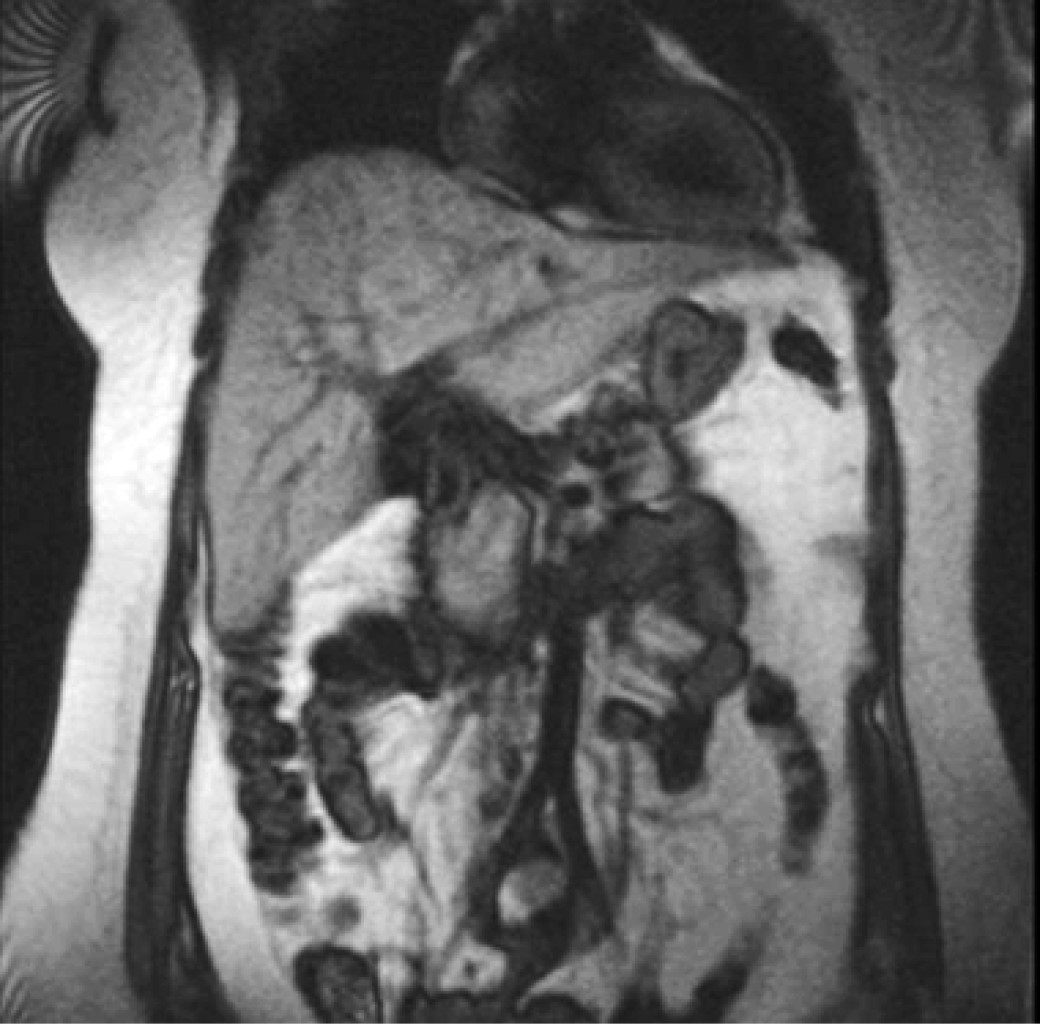

A 29-year-old female patient with no previous history of importance, and a body mass index of 28.5 kg/m2, starts suffering from sudden pain in the right hypochondrium, radiating to the scapular region, so she goes to a hospital of the Instituto Mexicano del Seguro Social (IMSS), at Unidad Médica de Alta Especialidad (UMAE) No. 14, where using computed tomography (CT) and magnetic resonance imaging (MRI) she was diagnosed with an occupying lesion in the right hepatic lobe of 9 cm in its largest diameter (Figure 1), with no clinical or biochemical data of liver cirrhosis (total bilirubin (BT) 1.20 mg/dl, direct bilirubin (BD) 0.7 mg/dl, total protein 5.4 g/dl, albumin 3.4 g/dl prothrombin time 14.4 seconds, international normalized ratio (INR) 1.08, platelets 217 × 103 cell/mm3) and serum alpha-fetoprotein 4 ng/ml.

Figure 1